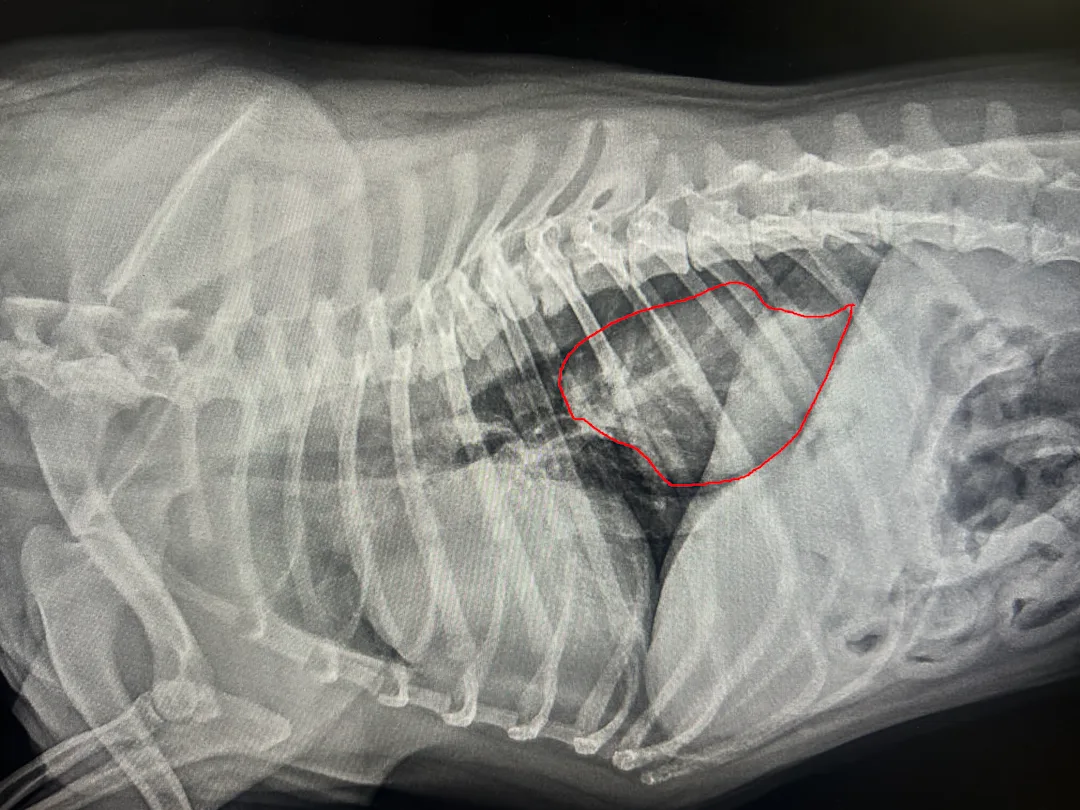

Hiatal Hernias:

IMG 5716 2 with red line

This is where the stomach “slides” through the opening where the esophagus meets the stomach. It’s particularly common in brachycephalic breeds (flat-faced dogs like Bulldogs) because the pressure from their obstructed breathing can literally “suck” the stomach into the chest.